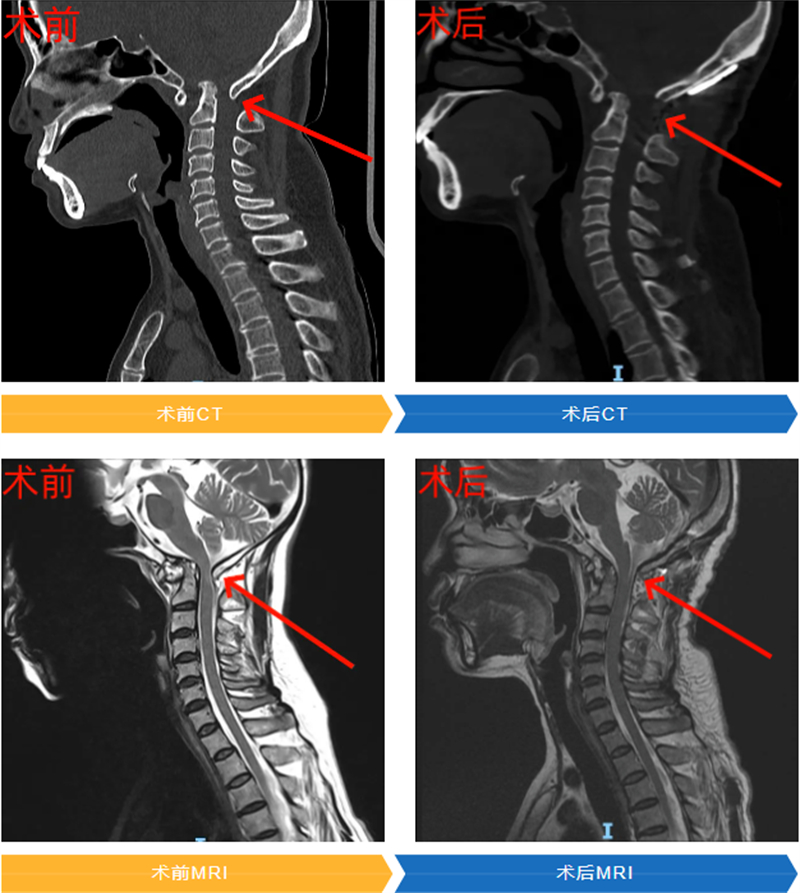

針對(duì)上述難點(diǎn),團(tuán)隊(duì)采用了代表當(dāng)前復(fù)雜顱頸交界畸形治療前沿的后路寰樞椎關(guān)節(jié)間撐開融合術(shù)。

該技術(shù)核心優(yōu)勢(shì)在于:通過單一后路切口即可完成關(guān)節(jié)松解、準(zhǔn)確復(fù)位、植入融合器并固定等所有關(guān)鍵步驟,避免了傳統(tǒng)前后路聯(lián)合手術(shù)的多重創(chuàng)傷、高感染風(fēng)險(xiǎn)及漫長(zhǎng)恢復(fù)期,體現(xiàn)微創(chuàng)精準(zhǔn)理念;融合器能維持復(fù)位后間隙,恢復(fù)解剖高度、解除神經(jīng)壓迫并提供植骨床,結(jié)合釘棒固定實(shí)現(xiàn)即刻穩(wěn)定與長(zhǎng)期融合,大幅降低復(fù)位丟失和再脫位風(fēng)險(xiǎn)。

在周密術(shù)前準(zhǔn)備和手術(shù)計(jì)劃保障下,手術(shù)團(tuán)隊(duì)順利完成這一高難度四級(jí)手術(shù)。

術(shù)后,韋女士恢復(fù)情況令人欣喜。在脊柱外科醫(yī)護(hù)團(tuán)隊(duì)的精心治療與護(hù)理下,術(shù)后僅第三天,她就能在輔助下行走,長(zhǎng)期困擾的后頸部疼痛和肢體麻木等癥狀得到緩解。